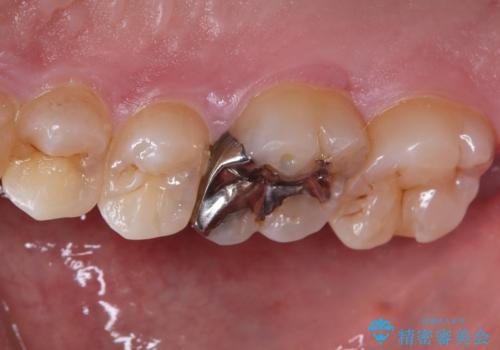

- 保険診療で治療した銀歯のやり替え希望の患者様です。

銀歯とその下の虫歯を除去し、形を整え、精度の良いシリコーンによる型どりを行いました。

セラミックインレーを接着する際は、ラバーダム防湿を行いました。